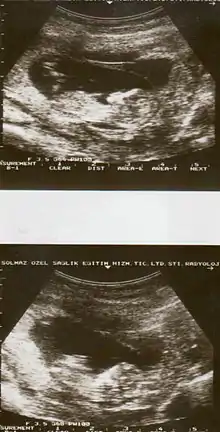

![]() | |

| Drawing of internal and external bleeding from placental abruption | |

| Diagnostic method | Based on symptoms, ultrasound[1] |

The cause of placental abruption is not entirely clear.[2] Risk factors include smoking, preeclampsia, prior abruption, trauma during pregnancy, cocaine use, and previous cesarean section.[2][1] Diagnosis is based on symptoms and supported by ultrasound.[1] It is classified as a complication of pregnancy.[1]

Placental abruption is suspected when a pregnant mother has sudden localized abdominal pain with or without bleeding. The fundus may be monitored because a rising fundus can indicate bleeding. An ultrasound may be used to rule out placenta praevia but is not diagnostic for abruption. The diagnosis is one of exclusion, meaning other possible sources of vaginal bleeding or abdominal pain have to be ruled out in order to diagnose placental abruption.[5] Of note, use of magnetic resonance imaging has been found to be highly sensitive in depicting placental abruption, and may be considered if no ultrasound evidence of placental abruption is present, especially if the diagnosis of placental abruption would change management.[14]